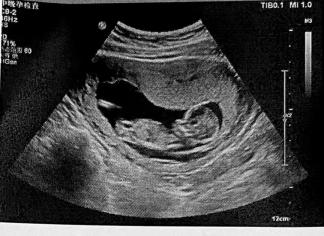

这一天,大街小巷处处上演着爱情电影:快递员飞奔着送鲜花,准夫妻排着队等着结婚登记,准爸妈小心翼翼地去做产检……商场里首饰服饰柜台各种热闹,饭店宾馆各种预订赠送……